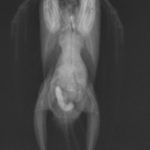

当院はウサギ・小動物・爬虫類・鳥類などのエキゾチックアニマル専門の病院です。

エキゾチックアニマルの診療

専門的なエキゾチックアニマル診療を提供しています。爬虫類、鳥類、小動物など、幅広い種類に対応。専門知識と経験を活かしたケアを提供。

ヒョウモントカゲモドキ、クサガメなどはこちら